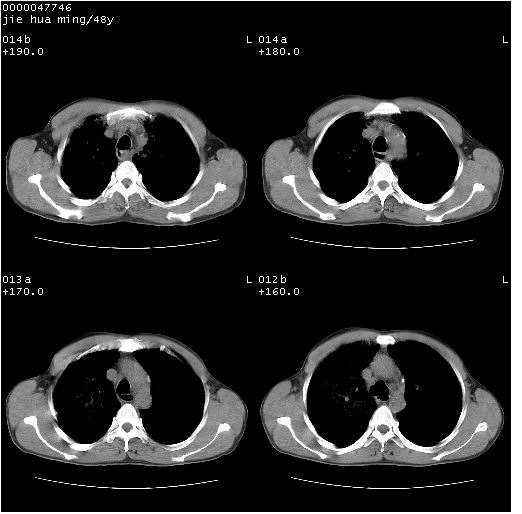

以下是引用dr.yang在2008-5-1 6:25:00的发言:[br]两肺广泛毛玻璃样的片状影,密度不均,边缘欠清,呈碎石路样改变,[br]考虑,1双肺间质性肺炎,2肺泡蛋白沉积症3支气管肺泡癌[br]

以下是引用hhcckk在2008-5-1 8:06:00的发言:[br]支持肺泡蛋白沉积症[br]依据:[br]1、病灶边缘清楚----地图征[br]2、病灶内部小叶间隔或小叶内间隔增厚所形成的网格状影----碎石路样表现[br]3、抗炎治疗无效(炎症抗炎治疗有效)[br]4、纵隔内未见肿大淋巴结(肺泡细胞癌时常有)[br][br]附肺泡蛋白沉积症资料[br][br]肺泡蛋白沉积症(pulmonary alveolar proteinosis)是一种原因不明的以肺泡腔内大量含脂糖蛋白样物质沉积为特征的疾病。[br]病理改变:(1)肺泡和细支气管腔内充满大量含脂糖蛋白样的粘稠物质,该物质为颗粒状或絮状的糖原pas染色阳性的磷脂蛋白。(2)肺泡壁及其间隔无异常改变。胸膜和淋巴结不受累及。(3)晚期可出现弥漫性肺间质纤维化。[br]临床表现:(1)好发年龄30~50岁,男性多于女性,偶见于儿童;(2)主要症状为呼吸困难、咳嗽、低热、消瘦、低氧血症和杵状指等。1/3的患者无症状。(3)实验室检查:痰液或肺泡灌洗液中可找到pas染色阳性颗粒物质。[br]hrct表现:肺泡蛋白沉积症具有特征性改变,即“碎石路样”表现(crazy-paving appearance,cpa)。主要包括(1)斑片状磨玻璃影:指肺野密度朦胧增加,内可见肺血管纹理影,系肺泡腔内充满低密度的磷脂蛋白物质所致。(2)其内部小叶间隔或小叶内间隔增厚所形成的网格状影,为小叶间隔水肿、肺泡壁内淋巴细胞和巨噬细胞浸润以及小叶内淋巴管扩张的缘故。(3)病灶边缘清楚,呈地图样分布于肺野外围或肺门及中央区。[br]

以下是引用zsl6918在2008-5-1 7:35:00的发言:[br]双肺磨玻璃样病变,可见铺碎路石征,病变区与正常区交错。边界清晰。符合肺泡蛋白质沉着征,高分辨扫描会更清楚漂亮。建议临床肺泡灌洗。

以下是引用yangyudong333在2008-5-1 5:36:00的发言:[br][br] 两肺广泛毛玻璃样的片状影,密度不均,边缘欠清,呈碎石路样改变,[br]考虑,1双肺间质性肺炎,2肺泡蛋白沉积症[br]